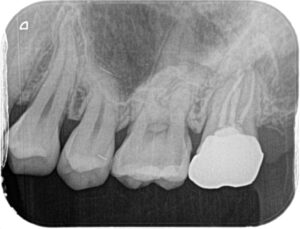

虫歯が隠れていそうな気配があったため小さいレントゲンを撮りました。

やっぱりありました!